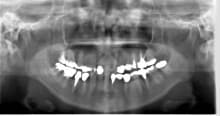

歯周病専門治療を行った症例をご紹介します。

写真を見ると、歯磨きは、とても気を付けて行っていたように思います。

では、なぜ歯周病で歯茎は腫れ、虫歯ができてしまったのか・・・

今回のケースも歯周専門治療にLADを併用して、

歯茎の発赤や腫れは、改善されました。

歯茎が引き締まった事で、新たな虫歯も発見されましたが、